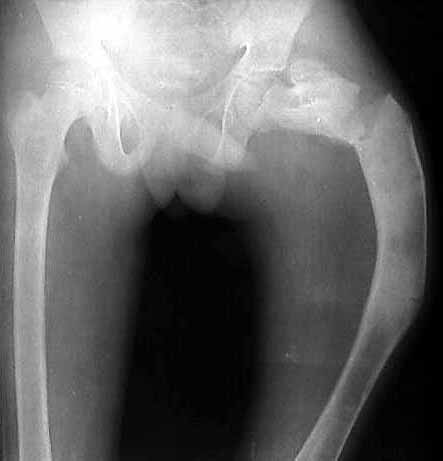

I am seeking help in managing a young patient 14 years old male with pathological subtrochanteric fracture neck femur. the problem is the severe varus deformity of the proximal femur the so called shepherd's crook deformity and also healing fracture shaft femur in midshaft region which he had sustained 6 months ago and was treated conservatively elsewhere. patient wants his deformity correction along with his fracture treatment if possible.

photo

no txn